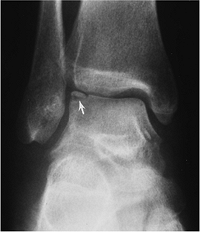

Fractures/Dislocations: Ankle Fractures—Pediatric: Juvenile Tillaux

-

Distal tibial epiphysis fuses from medial to lateral, placing the lateral physis at risk in adolescents.

Distal tibial physis fuses at approximately age 15 years in females and age 17 years in males.

Juvenile Tillaux fracture is a Salter-Harris Type III fracture of the lateral tibial physis.

The fracture is displaced by the distal tibio-fibular ligament when the foot is externally rotated.

![]() |

|

FIGURE 6-7 AP radiograph shows a Salter-Harris III fracture—juvenile Tillaux fracture (arrows).